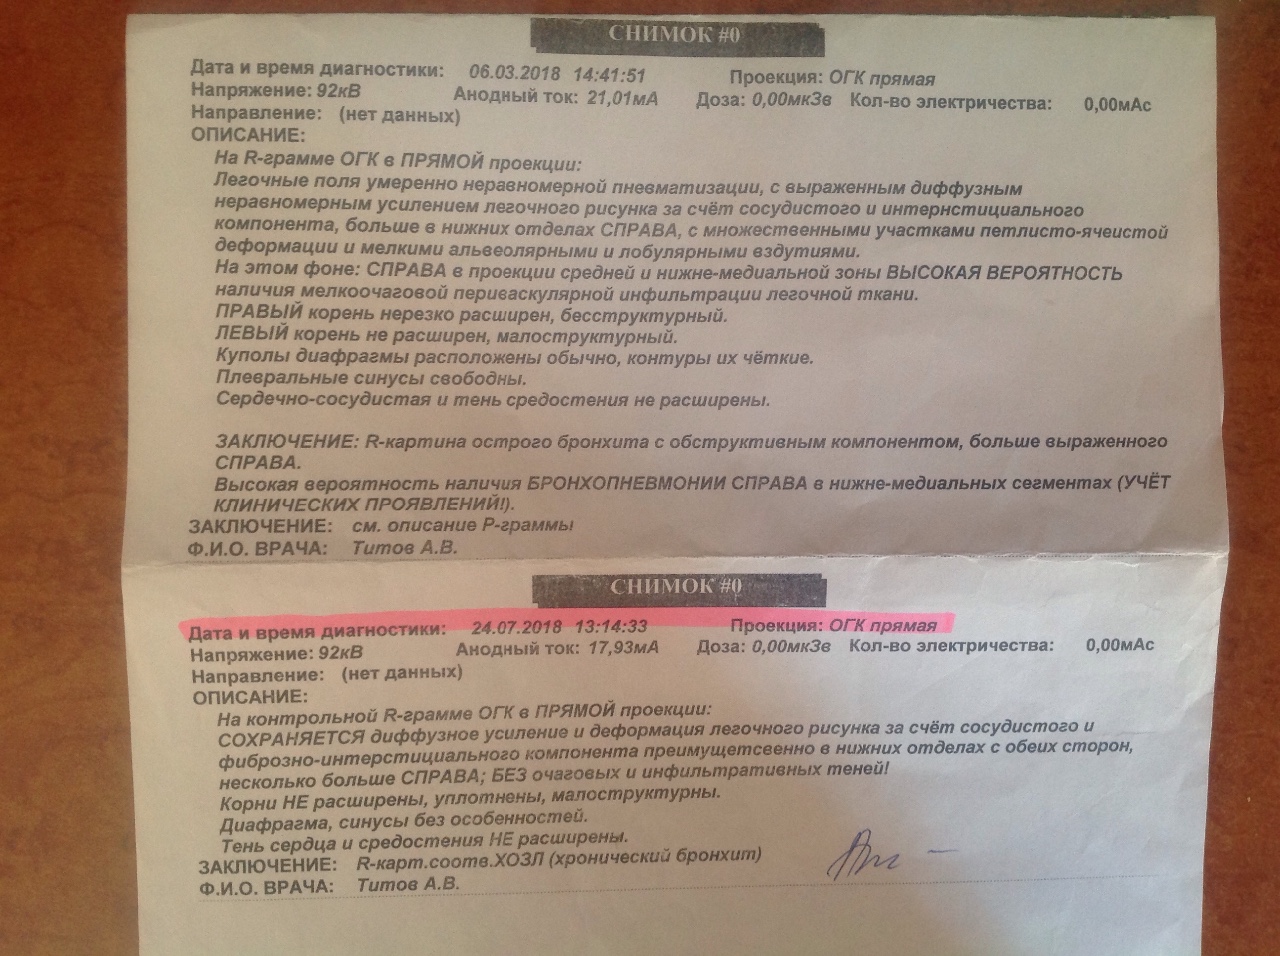

Рентгенодиагностика бронхопневмонии: Советы и примеры

Раздел: Альбом открытий